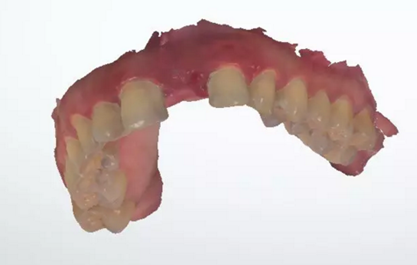

術(shù)前檢查

1.術(shù)前CT